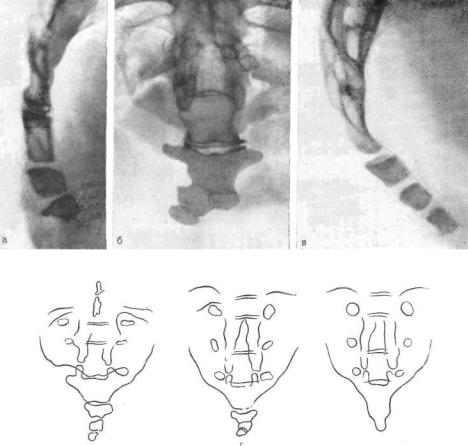

Рентгеновские снимки крестцово-копчикового отдела позвоночника